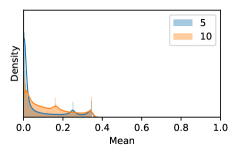

In contrast, the MC-dropout method showed the worst overall performance among the three, as it can be seen from the high ratios of SL0 examples among the uncertain negatives in Figure 4. The histograms in Figure 2 provides another perspective to look into the phenomenon, where a decent proportion of MC-dropout model’s predictions on SL0 inputs entailed low confidence (far from 0 or 1), which from another angle explained why MC-dropout was less specific in terms of lower FNP; many no-DR inputs (i.e. SL0) were erroneously assigned high uncertainty by MC-dropout models.

It is still an open question why the evaluated MC-dropout networks signaled relatively high uncertainty on SL0 & SL3 & SL4 data that are less likely to be ambiguous. We conjecture that much of the “uncertainty” indicated by disagreement among test-time dropout samples actually reflects the stochastic nature of dropout networks rather than the real decision uncertainty associated with the data. It is worth noting that the MC-dropout model we evaluated was not weak per se; they all achieved above Area Under Curve (AUC) scores on test sets. The weakness of individual test-time samples (which explains their low-confidence predictions on SL0 & SL3 & SL4) might have been hidden when they are aggregated into an ensemble—a well-known advantage of ensemble learning. Our results suggested that the uncertainty information given by implicit ensemble methods such as MC-dropout and TTA might not be as reliable as that from explicit ensemble approaches (e.g., stacking ensembles). Similar findings on MC-dropout can be found in some previous papers [1].

Most models reached an AUC above on both the training and the validation sets. We discarded the bad performing models and put the rest into a pool. The retained models in the pool were then used as base learners for constructing stacking ensembles. To create an ensemble model instance, we randomly picked single learners from the pool. In our experiment, we evaluated and , two ensemble sizes used in previous works [1, 24]. Their individual predictions were then combined and grouped for later analysis.